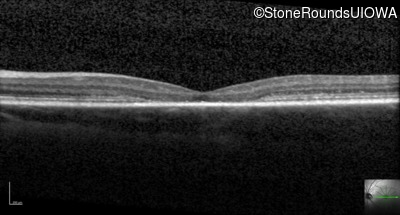

Optical Coherence Tomography - Left - 20/80 -1

Exemplar / OCT Stack

OCT Stack